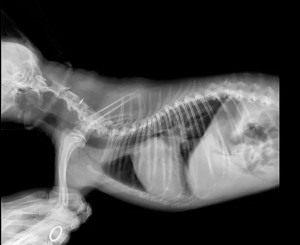

临床检查:精神状态很差,,听诊二尖瓣重度反流,心杂音重,站立不稳

BCS 5/9 体温37.5度,呼吸一分钟80次

肺水肿,二尖瓣退行性病变MMVD C期